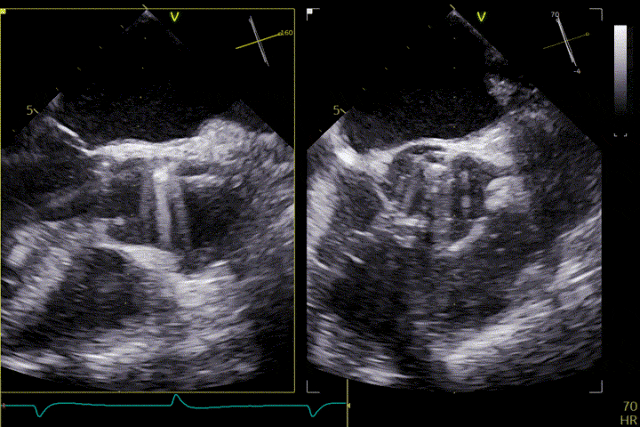

術前超聲

輸送器跨瓣

打開定位件

定位件入竇

瓣膜釋放

術后效果

患者主動脈瓣重度反流糾正,術后無反流、無瓣周漏。術后心臟彩超顯示人工生物瓣啟閉良好,平均跨瓣壓差2mmHg,流速正常。患者恢復情況良好,心功能較術前有了明顯改善。